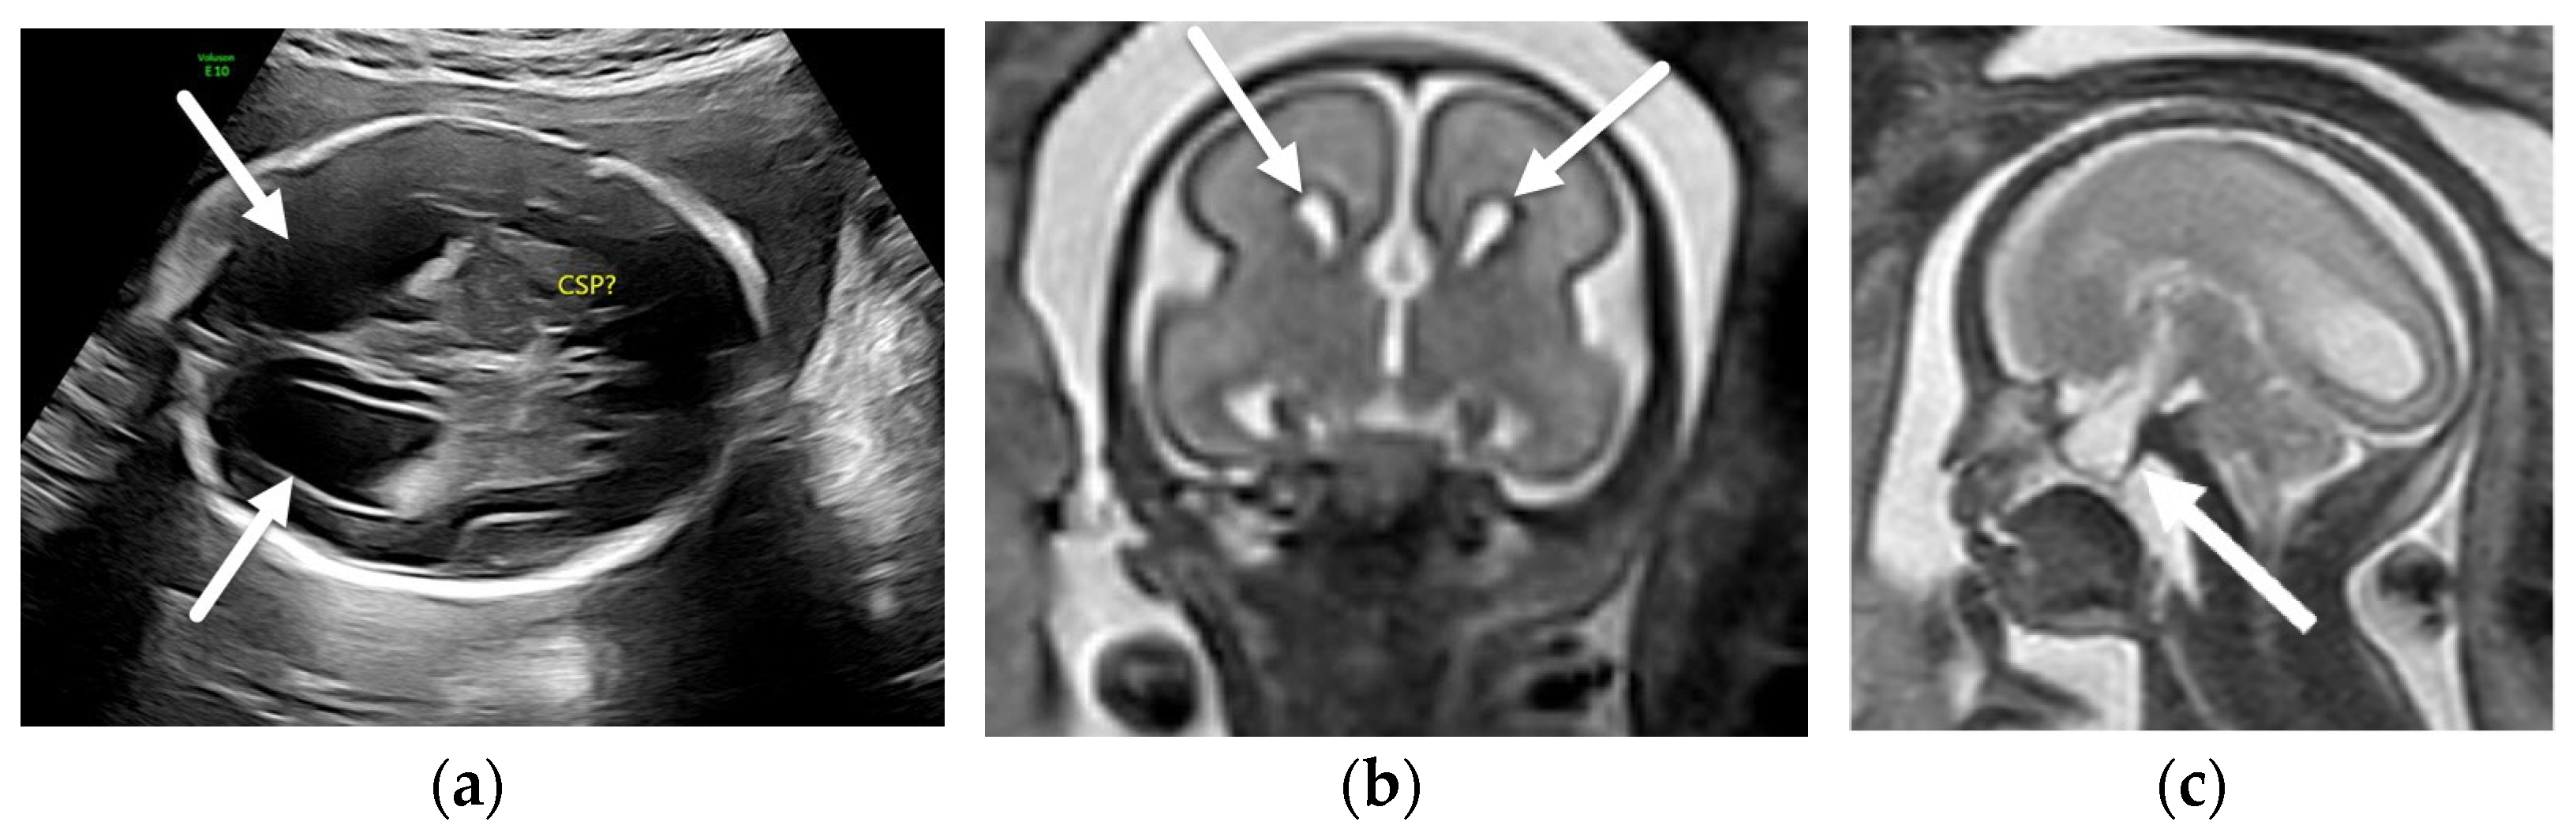

3.1.2. Chiari II Malformation

- Stevenson, K.L. Chiari Type II malformation: Past, present, and future. Neurosurg. Focus 2004, 16, 1–7. [Google Scholar] [CrossRef]

- Van den Hof, M.C.; Nicolaides, K.H.; Campbell, J.; Campbell, S. Evaluation of the lemon and banana signs in one hundred thirty fetuses with open spina bifida. Am. J. Obstet. Gynecol. 1990, 162, 322–327. [Google Scholar] [CrossRef]

- Sutton, L.N.; Adzick, N.S.; Bilaniuk, L.T.; Johnson, M.P.; Crombleholme, T.M.; Flake, A.W. Improvement in hindbrain herniation demonstrated by serial fetal magnetic resonance imaging following fetal surgery for myelomeningocele. J. Am. Med. Assoc. 1999, 282, 1826–1831. [Google Scholar] [CrossRef] [Green Version]

- Nagaraj, U.D.; Bierbrauer, K.S.; Zhang, B.; Peiro, J.L.; Kline-Fath, B.M. Hindbrain Herniation in Chiari II Malformation on Fetal and Postnatal MRI. AJNR Am. J. Neuroradiol. 2017, 38, 1031–1036. [Google Scholar] [CrossRef] [PubMed] [Green Version]